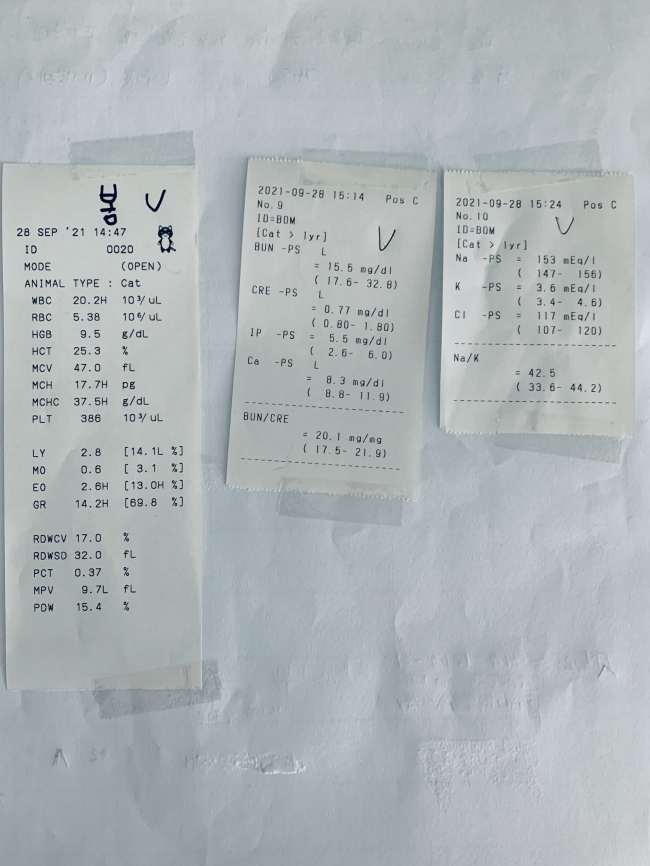

사진첨부

치료전 대상묘

치료중 대상묘

치료완료후